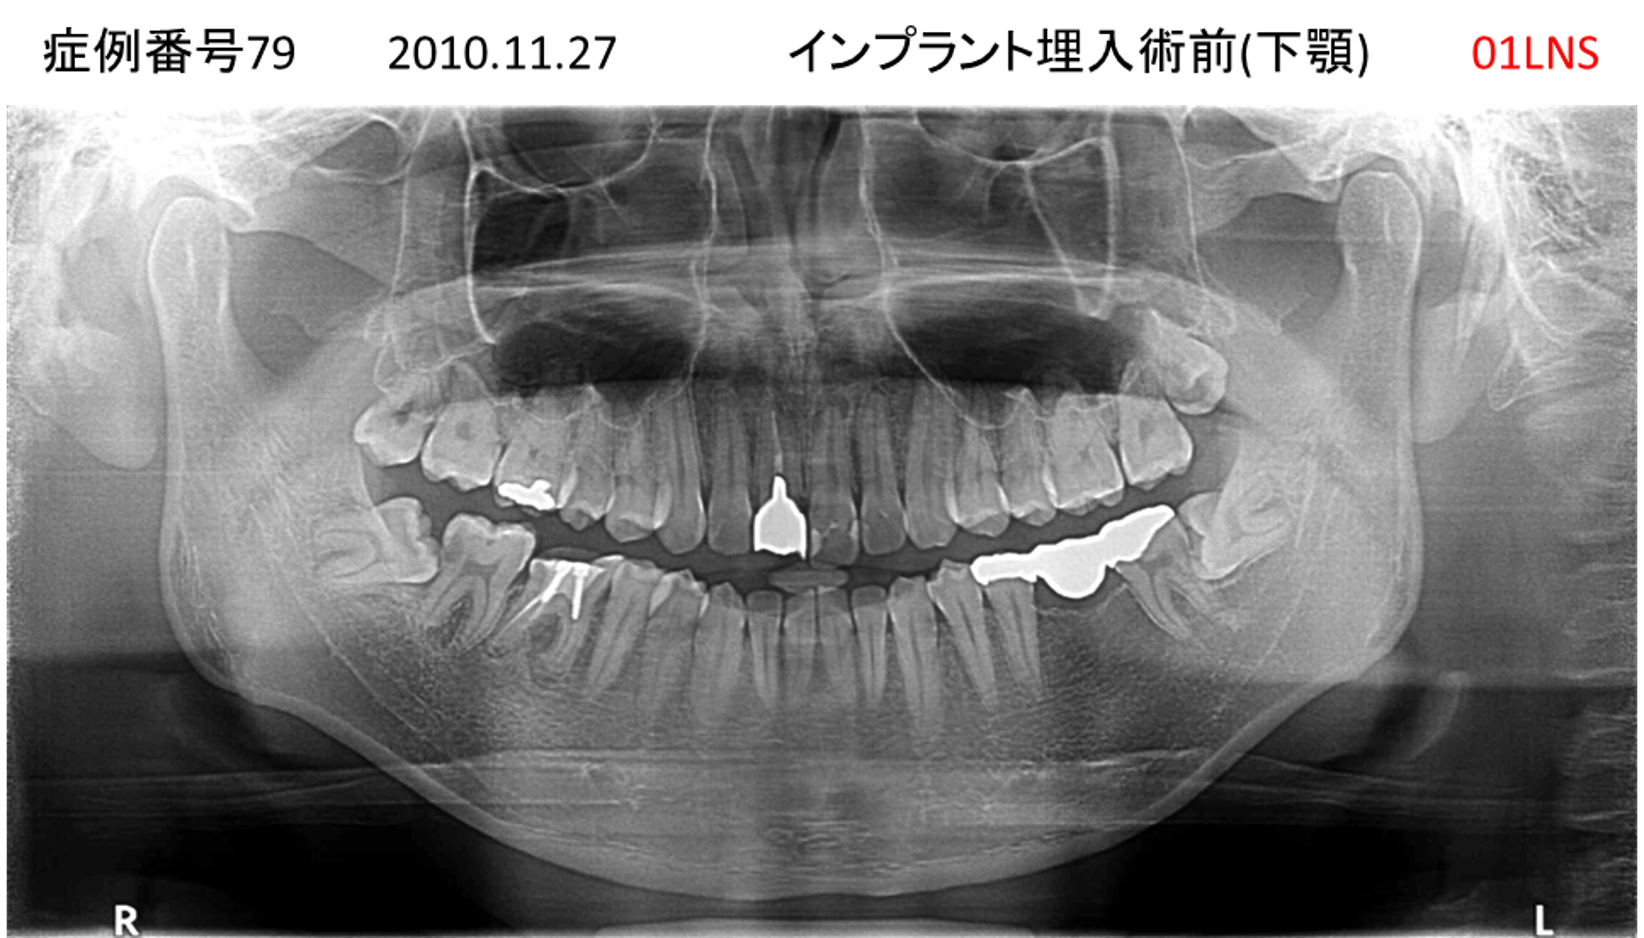

左下の歯が痛い患者様のインプラント症例

| 治療名称 |

インプラント |

| 治療費用 |

330万円+税 |

| 治療期間 |

4か月 |

| 患者さんの症状(主訴) |

左下の歯が痛い |

| 治療内容 |

サイナスリフト 抜歯即時インプラント |

| 治療結果 |

食事に困らない。見た目がとても良くなった。 |

| 治療の注意点(リスク/副作用) |

インプラントが壊れたら再治療が必要 |